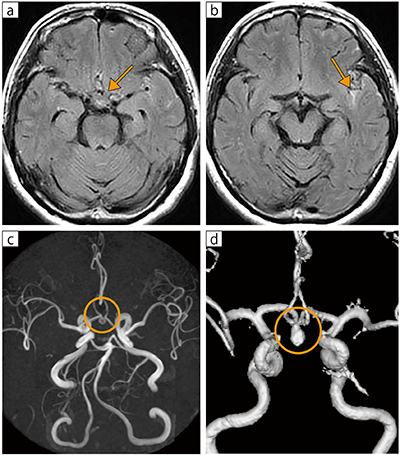

■症例1:クモ膜下出血

64歳,女性。受診2日前の入浴中に突然の頭痛と両足硬直があり,その後,頭痛と吐き気が続くため受診。神経学的には異常所見を認めなかったが,頭部MRIのFLAIRにてクモ膜下腔に出血(←)を認め,MRAにて脳動脈瘤(○)が確認された。

a,b:FLAIR,RADAR,AX,TR/TE=10000/90,FA:90°,スライス厚:5mm

c:MRA,MIP-HF, AX,TR/TE=20.7/6.9,FA:20°,スライス厚:1.2mm

d:MRA,VR,TR/TE=20.7/6.9,FA:20°,スライス厚:1.2mm〔INTAGE Realia Professional(サイバネット社製)にて再構成〕